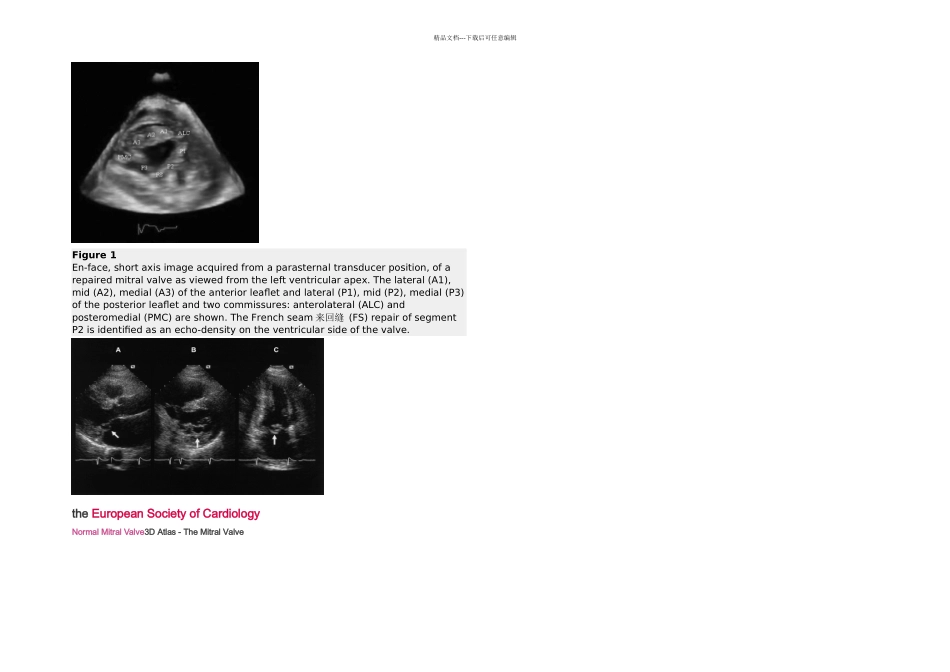

精品文档---下载后可任意编辑Figure 1En-face, short axis image acquired from a parasternal transducer position, of a repaired mitral valve as viewed from the left ventricular apex. The lateral (A1), mid (A2), medial (A3) of the anterior leaflet and lateral (P1), mid (P2), medial (P3) of the posterior leaflet and two commissures: anterolateral (ALC) and posteromedial (PMC) are shown. The French seam 来回缝 (FS) repair of segment P2 is identified as an echo-density on the ventricular side of the valve. the European Society of CardiologyNormal Mitral Valve3D Atlas - The Mitral Valve